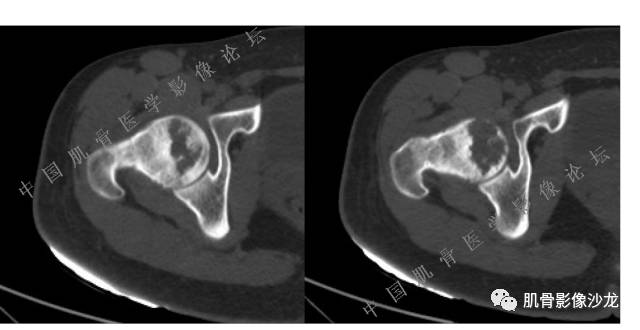

主诉:右大腿疼痛、活动受限20天

现病史:患者于20天前无明显诱因出现右下肢疼痛,活动受限,疼痛呈阵发性,活动后加重。自行口服止痛药芬必得,效果不佳,至当地医院治疗,检查发现右侧股骨近端病变。遂来诊

葛英霖 20:30 原发或继发动脉瘤样骨囊肿,继发于巨细胞瘤,软骨母,纤维组织细胞瘤,骨母等等

向以四 20:30 软骨母合并ABC,

医影在线 20:30 软骨母,/继发ABC

飞鹰行动 20:31 T2信号高,有软骨成分

Echo 20:32 T2确实有一块区域很亮 ,并有野液平

飞鹰行动 20:33 有侵袭性

飞鹰行动 20:35 骨皮质破坏,周围骨质异常信号

葛英霖 20:36 这不是良性病变

葛英霖 20:36 中间型可能性极大

葛英霖 20:37 明显侵蚀骨内膜啊,硬化边也不完整 (细箭头所示)

葛英霖 20:43 提不提也很明显继发了abc

葛英霖 20:44 是

葛英霖 20:46 明显的多囊状改变,液液平面